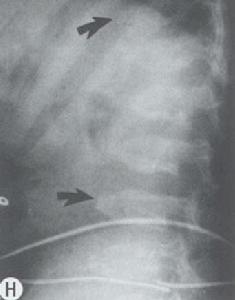

(三)外胚層組織營養變性及異常鈣化症群如甲狀旁腺功能減退為時過久,常發現皮膚粗糙,色素沉著、毛髮脫落,指(趾)甲脆軟萎縮,甚而脫落;眼內晶狀體可發生白內障。病起於兒童期者,牙齒鈣化不全,齒釉發育障礙,呈黃點、橫紋、小孔等病變。患兒智力多衰退、腦電圖常有異常表現,可出現癲癇樣波(不同於原因不明性癲癇,於補鈣後,癲癇樣波可消失):頭顱X線片可見基底節鈣化,骨質也較正常緻密,有時小腦亦可鈣化。